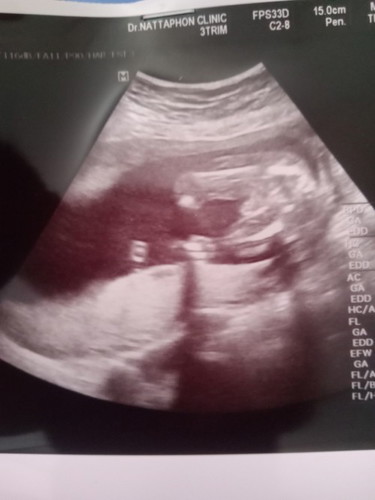

น้องเป็นผู้หญิงหรือผู้ชายค่ะ หมอบอกว่าผู้ชายค่ะ มีจู๋โผล่ค่ะ แม่ไม่มัดใจค่ะ

100%เลยค่าา